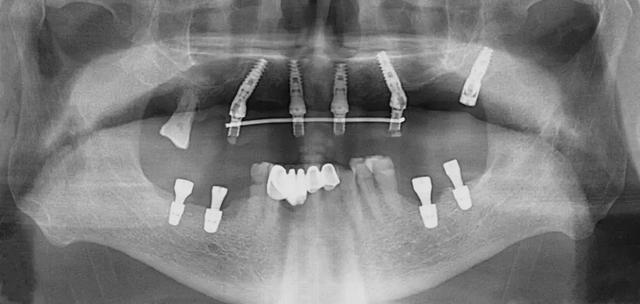

口腔科李德仁主任為老人仔細(xì)檢查了口腔情況,由于缺牙時間太久,牙床骨量極少,正常的種植修復(fù)需要植骨,手術(shù)創(chuàng)傷大而且半年后才能鑲牙吃飯。建議他進(jìn)行數(shù)字化導(dǎo)板種植,可以不用植骨而且當(dāng)天就能戴牙吃飯,手術(shù)簡單,創(chuàng)傷小。老人和孩子很信任的接受了李主任的種植方案:上牙床種植5顆,下牙床種植4顆,當(dāng)天戴牙吃飯。

下午2點(diǎn)開始手術(shù),歷經(jīng)90分鐘,一共植入9顆種植體,全程。下午7點(diǎn)用了10多分鐘就完成了假牙安裝,假牙與牙床渾然一體,像是重新長出的牙齒一般。

全口缺牙一日重建種植手術(shù)有以下優(yōu)點(diǎn):使用CT導(dǎo)板定位,在骨量好的位置種植,一般不需植骨,手術(shù)創(chuàng)傷小,手術(shù)時間短,愈合快,基本上沒有疼痛。拔牙同時種植牙,當(dāng)日戴臨時全口固定式假牙吃飯。